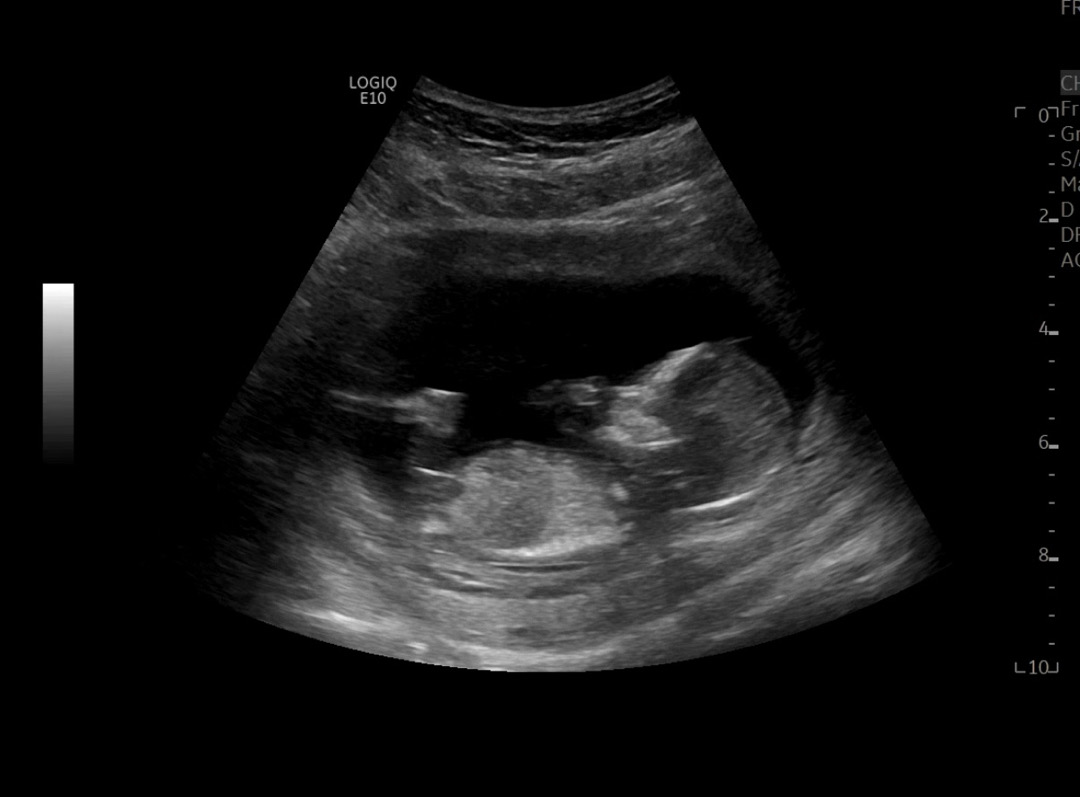

12주 6일 각도법 봐주세요 🥹

안녕하세여 ㅎㅎ 좀 흐릿한거 같지만 ㅠㅠ 12주 6일 각도법으로 알 수 있을까요...?

딸 같아요!!